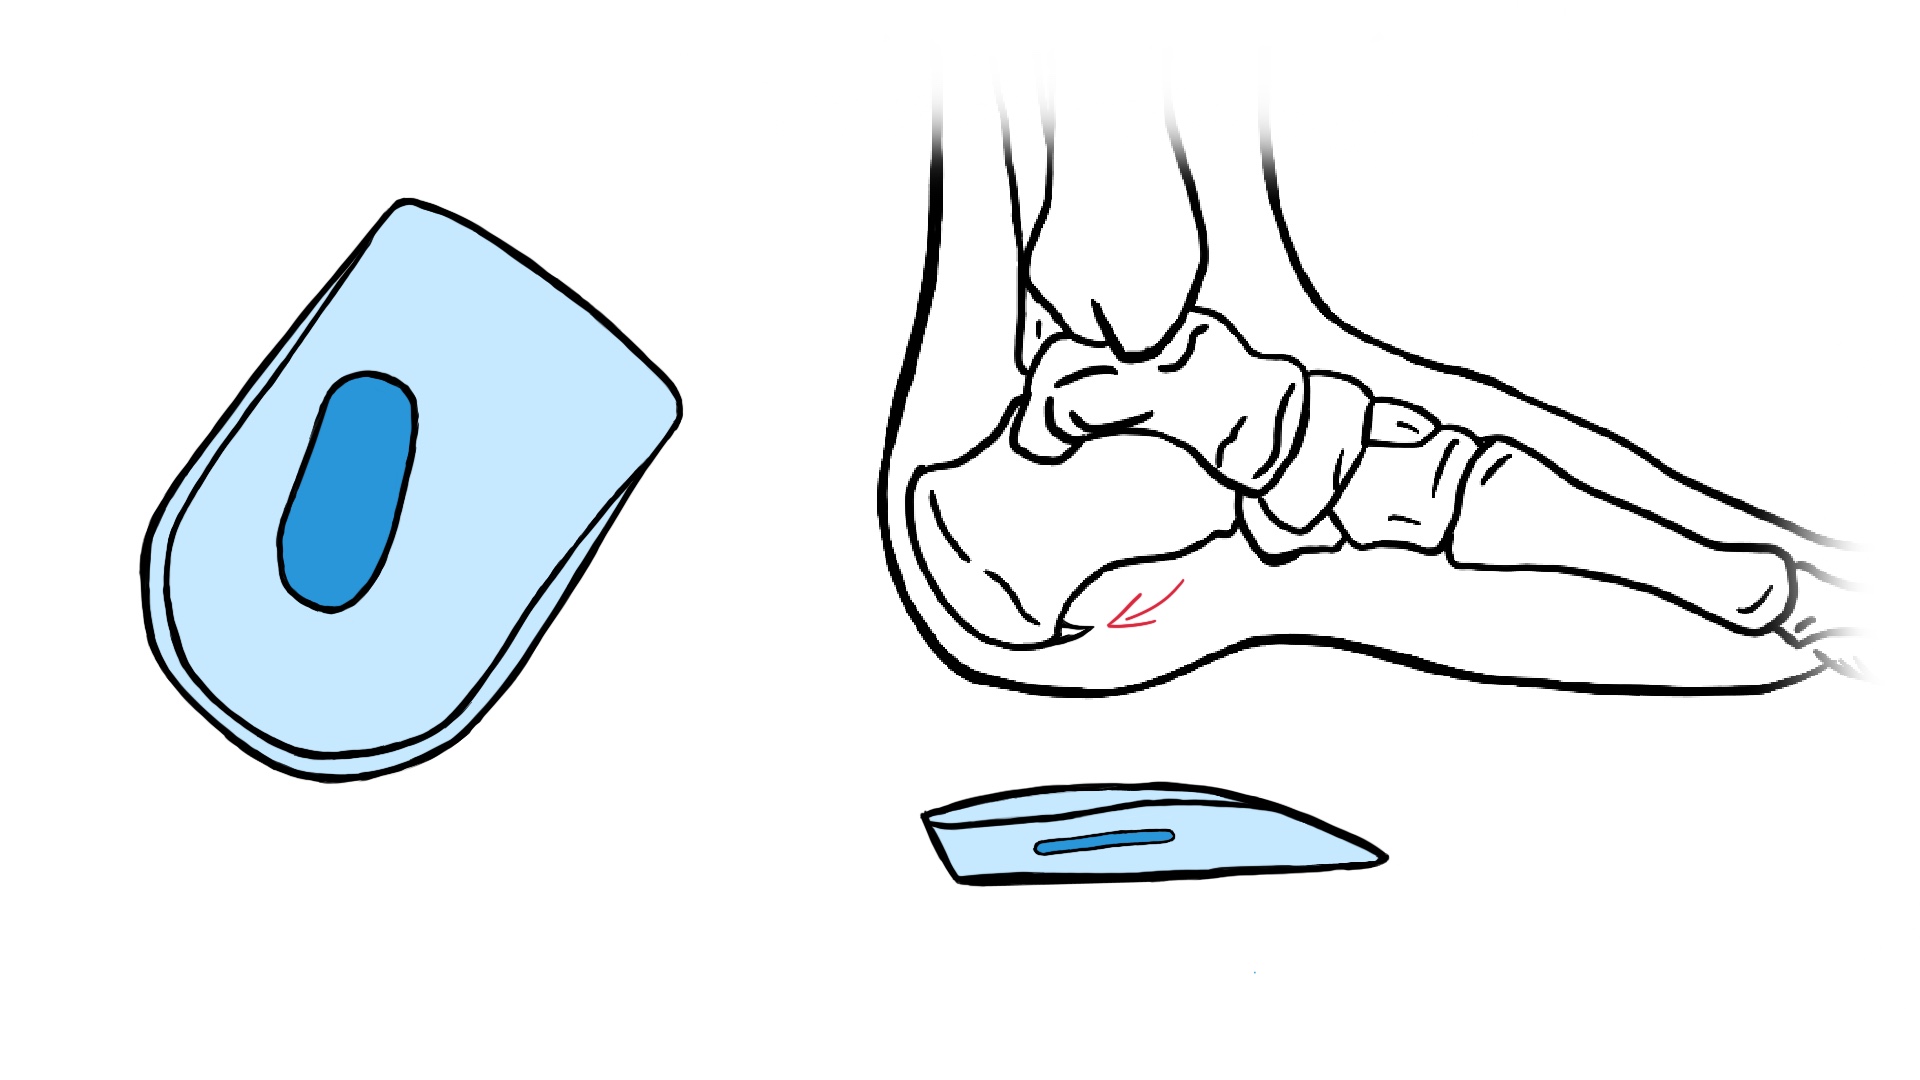

Behandlung des Fersensporns mit orthopädischen Einlagen

Wenn du dich mit dem Thema Fersensporn auseinandersetzt, hast du wahrscheinlich bereits von orthopädischen Einlagen gehört. Diese Einlagen oder auch Einlegesohlen genannt, werden in die Schuhe gelegt. Aber was genau sind diese speziellen Einlagen und wie können sie bei der Behandlung eines Fersensporns helfen?

- Individuelle Anfertigung orthopädischer Einlagen: Spezialisierte Schuheinlagen dienen zur Druckentlastung und Fußausrichtung/Fußkorrektur. Orthopädische Einlagen sind individuell angefertigte Schuheinlagen, die speziell auf deine Fußstruktur zugeschnitten werden. Sie dienen dazu, den Druck auf den betroffenen Bereich zu entlasten und die natürliche Ausrichtung und Stellung deines Fußes wiederherzustellen.

- Druckreduktion und Gewölbestützung: Gewichtsverteilung und Stabilisierung bei Fersensporn und Fußfehlstellungen. Ein Hauptziel der Therapie ist es, die schmerzhafte Belastung des Fersenbeins zu reduzieren. Orthopädische Einlagen können dabei eine wichtige Rolle spielen, da sie durch ihre maßgeschneiderte Formgebung eine gleichmäßige Lastverteilung ermöglichen und somit den Druck vom Sporn nehmen und besser auf die Fußsohle verteilen. Dies geschieht im Bereich der Ferse ähnlich wie beim Fersenkeil aus Silikon oder Gel, mit einem weichen Polster an der betroffenen Stelle. Darüber hinaus bieten orthopädische Einlagen auch Unterstützung für das gesamte Fußgewölbe. Dies kann besonders hilfreich sein, wenn ein flacher oder überpronierender (Fuß sinkt im Gewölbe ab und knickt im Sprunggelenk nach innen) Fußbau vorliegt – beides Risikofaktoren für die Entstehung eines Fersensporns.

- Einlagen als Teil der Gesamttherapie: Einbindung in ein umfangreiches Behandlungskonzept mit Physiotherapie und Medikation. Es ist wichtig anzumerken, dass orthopädische Einlagen alleine keine Wunderheilungen bewirken können. Sie sollten viel mehr als Teil eines umfassenden Behandlungsansatzes betrachtet werden, der auch physiotherapeutische Übungen zur Stärkung der Muskulatur sowie gegebenenfalls medikamentöse Therapiemaßnahmen umfasst.

- Wichtigkeit der fachgerechten Anpassung: Zusammenfassend lässt sich sagen, dass orthopädische Einlagen eine wirksame Behandlungsoption für Menschen mit Fersensporn darstellen. Durch ihre individuelle Anpassung an die Fußstruktur können sie den Druck auf den betroffenen Bereich reduzieren und zur Schmerzlinderung beitragen. Dennoch sollten sie stets in Verbindung mit anderen Therapiemaßnahmen verwendet werden, um optimale Ergebnisse zu erzielen.

Es ist wichtig zu betonen, dass jeder Patient einzigartig ist und die Behandlungsentscheidungen immer auf individueller Basis getroffen werden sollten, unter Berücksichtigung des gesamten klinischen Bildes und der Vorlieben des Patienten.